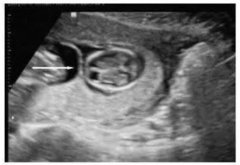

高危胎兒診治技術_雙胎妊娠超聲檢查技術規范

雙胎超聲檢查量亦呈上升趨勢, 據該項目組中具有代表性的中國醫科大學附屬盛京醫院統計: 2016年雙胎超聲檢查人次數(5235人次)是2013年 (1917人次)...